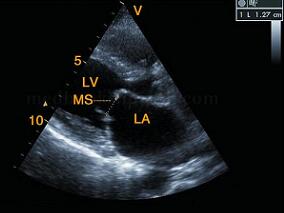

1小时条评论【病例1】 病史和相关检查 患者,女,42岁,主因呼吸困难、咳嗽、咯血就诊。查体:患者双颧紫红,于心尖部闻及低调的隆隆样舒张中晚期杂音,第一心音亢进和开瓣音,三尖瓣区闻及全收缩期吹风样杂音。X线:左房增大,后前位见左心缘变直,右心缘有双心房影。心电图:...